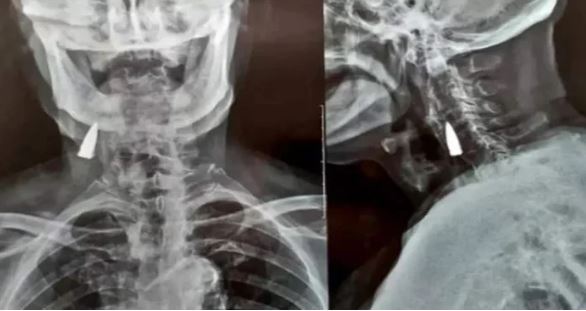

95 سالہ شخص کی گردن میں 77 سال سے گولی پھنسے کے باوجود بھی وہ صحت مند ہے

21 نومبر 202221 نومبر 2022 ویب ڈیسک 113 مناظر